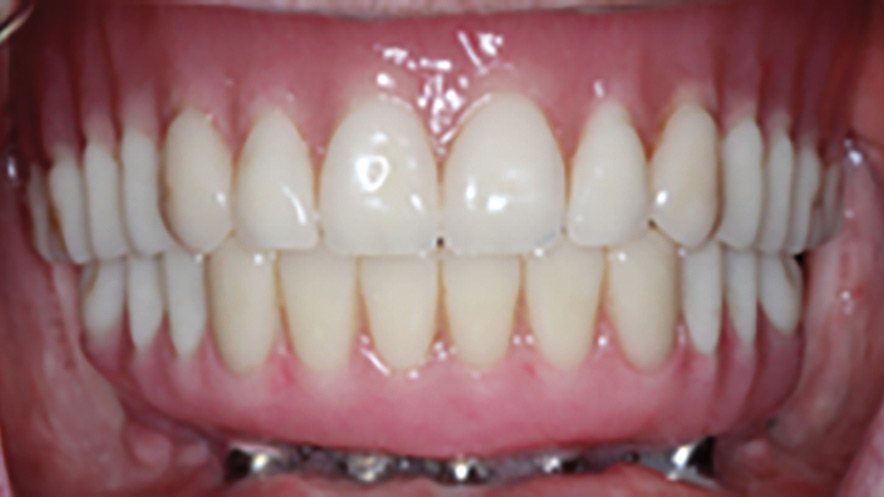

An Alternative Prosthetic Design for Lower Full-Arch Implant Restorations

Frontal view of finished prosthesis.

Replacing a full set of teeth with dental implants, especially in the mandible, has been well researched and is often a life-changing treatment for many patients. This treatment involves the extraction of failing teeth, immediate implant placement, immediate loading of the implants with a fixed provisional prosthesis, followed by the fabrication of a definitive prosthesis … Read more